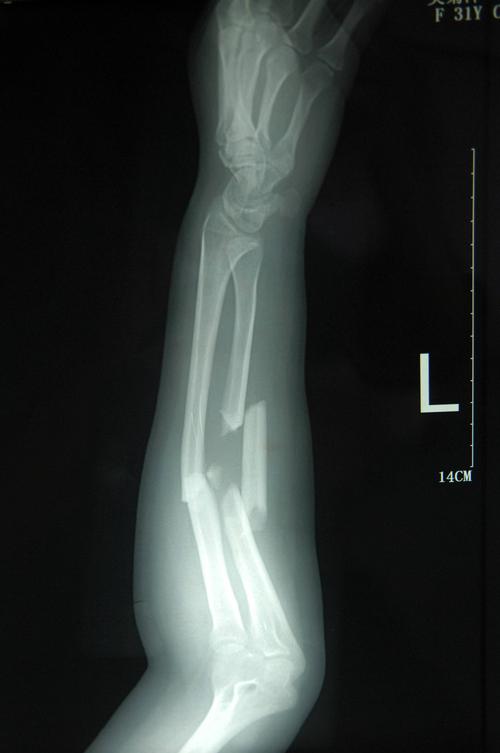

拍摄的吴菊萍受伤左臂的x光片,医生诊断为手臂左尺桡骨多段粉碎性骨折